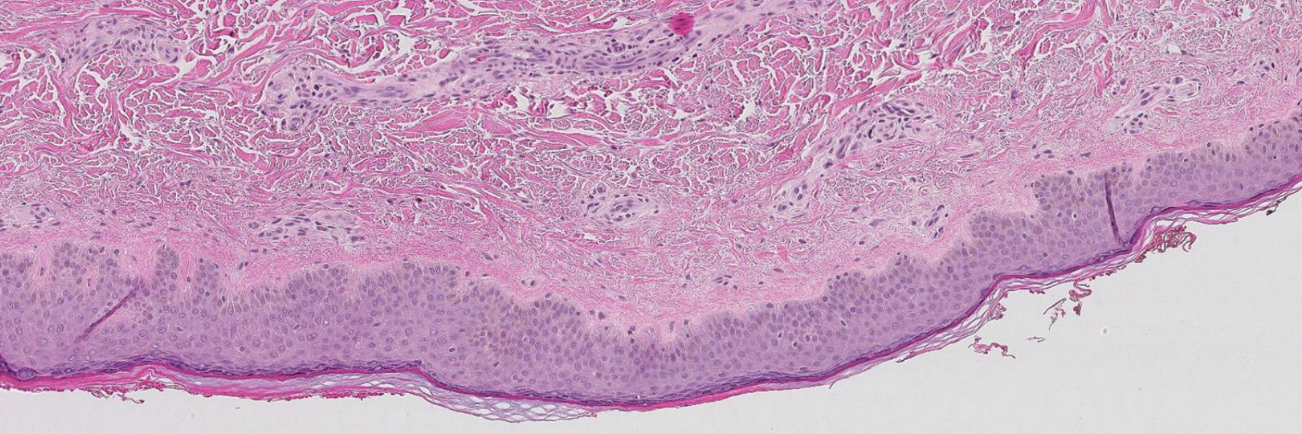

Patologiens morfologiske (struktur), immunhistokjemiske (proteiner) og molekylære analyser (arvestoff) er helt sentralt i arbeidet med kreftdiagnoser. Vi ønsker å forbedre patologidiagnostikken gjennom å finne, validere og ta i bruk nye biomarkører. Vi skal nå dette målet ved å ta i bruk storskala-analyser for proteiner og arvestoff, kunstig intelligens og digital patologi.

Livmorhalskreft

- "Who are at risk of developing cervical cancer?" Utvikling av nye biomarkører som kan forutsi hvilke kvinner som har risiko for å utvikle livmorhalskreft. Fokus på immunforsvar og genetiske endringer i vevet. Samarbeidsprosjekt med Kreftregisteret og Sørlandet sykehus.